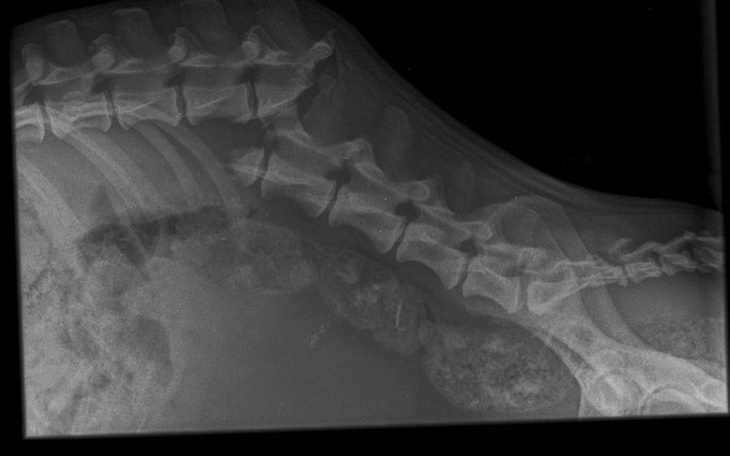

Jesteśmy Fundacją na Rzecz Zwierząt Nie_zły pies. Ratujemy bezdomne, krzywdzone, zaniedbane zwierzęta. Pod koniec stycznia we wsi pod Grójcem znaleziono psa, który poruszał sie tylko na przednich łapach. Zabraliśmy go do weterynarza . Okazało się, ze pies ma złamany kręgosłup w części lędźwiowej. Pierwszą decyzją była eutanazja, ale pies miał tak wielką chęć życia , że po wielu konsultacjach z ortopedami postanowiliśmy dać mu szansę na nowe życie.

1 lutego odbyła się operacja zespolenia kręgosłupa, ale rdzeń jest przerwany i pies nie będzie chodził. Potrzebny jest wózek ortopedyczny i rehabilitacja.